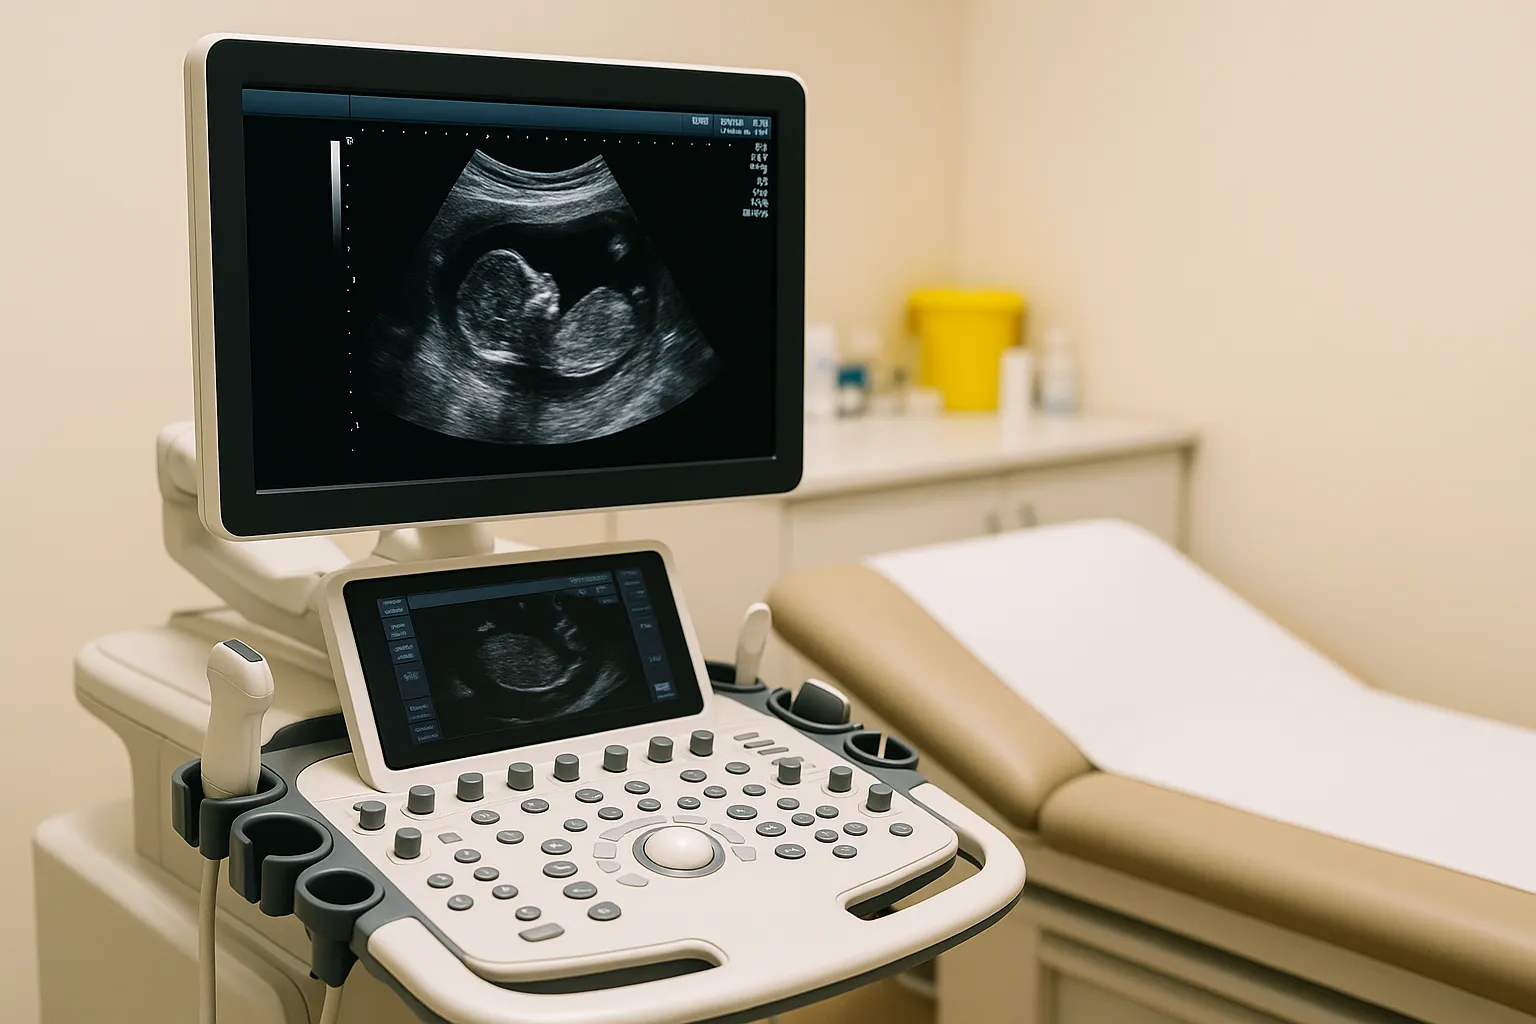

Concerns have been raised by leading radiographers regarding the presence of “unsafe” high street clinics offering ultrasound scans for expectant parents, amid alarming reports of serious misdiagnoses and overlooked medical emergencies. The Society of Radiographers (SoR) has indicated that an increasing number of these private establishments are providing pregnancy scans, often staffed by personnel who lack the necessary training and qualifications.

According to the SoR, the lack of regulation allows anyone with access to an ultrasound machine to label themselves as a sonographer, a significant deviation from the standards required of other healthcare professionals who must undergo proper training before practicing. This unregulated environment poses considerable risks to both mothers and their babies, potentially leading to life-threatening situations.

The SoR is advocating for the establishment of a “protected” title for sonographers. This measure would ensure that only individuals who are properly qualified and registered with a recognised regulatory body can designate themselves as sonographers. Katie Thompson, president of the SoR and an experienced hospital sonographer, emphasised the public’s assumption that individuals performing scans are appropriately qualified. “When people go for a scan or any kind of diagnostic test, they assume that the person they’re going to see is qualified to do it. They don’t realise that anybody can buy a machine and call themselves a sonographer,” she explained. With a formal registration, patients would have recourse to a regulatory body should any issues arise.